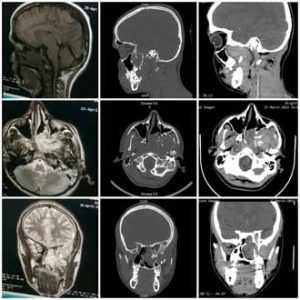

ولفتت الدكتورة الجاسم إلى أنه عند اجراء تنظير للأنف تبين وجود كتلة محمرة متينة تملأ جوف الأنف الأيسر في منطقة الصماخ المتوسط والسفلي ممتدة نحو الخلف مسببة انحرافاً شديداً في الحاجز الأنفي نحو الطرف المقابل مع وجود خثرات دموية على سطح الكتلة.

وبعد إجراء الاستقصاءات الشعاعية اللازمة بينت الدكتورة الجاسم أن صورة الطبقي المحوري مع الحقن أظهرت آفة غير متجانسة تملأ جوف الأنف الأيسر ممتدة للحفرة الجناحية الحنكية وصولاً للحفرة تحت الصدغية مع تورم بسيط للجيب الوتدي إضافة إلى ملاحظة تقوس الجدار الخلفي للجيب الفكي فيما بينت صورة المرنان المغناطيسي مع الحقن أن الآفة لا تغزو النسيج الدماغي وتم تصنيف الورم من النوع الثاني- الثالث.